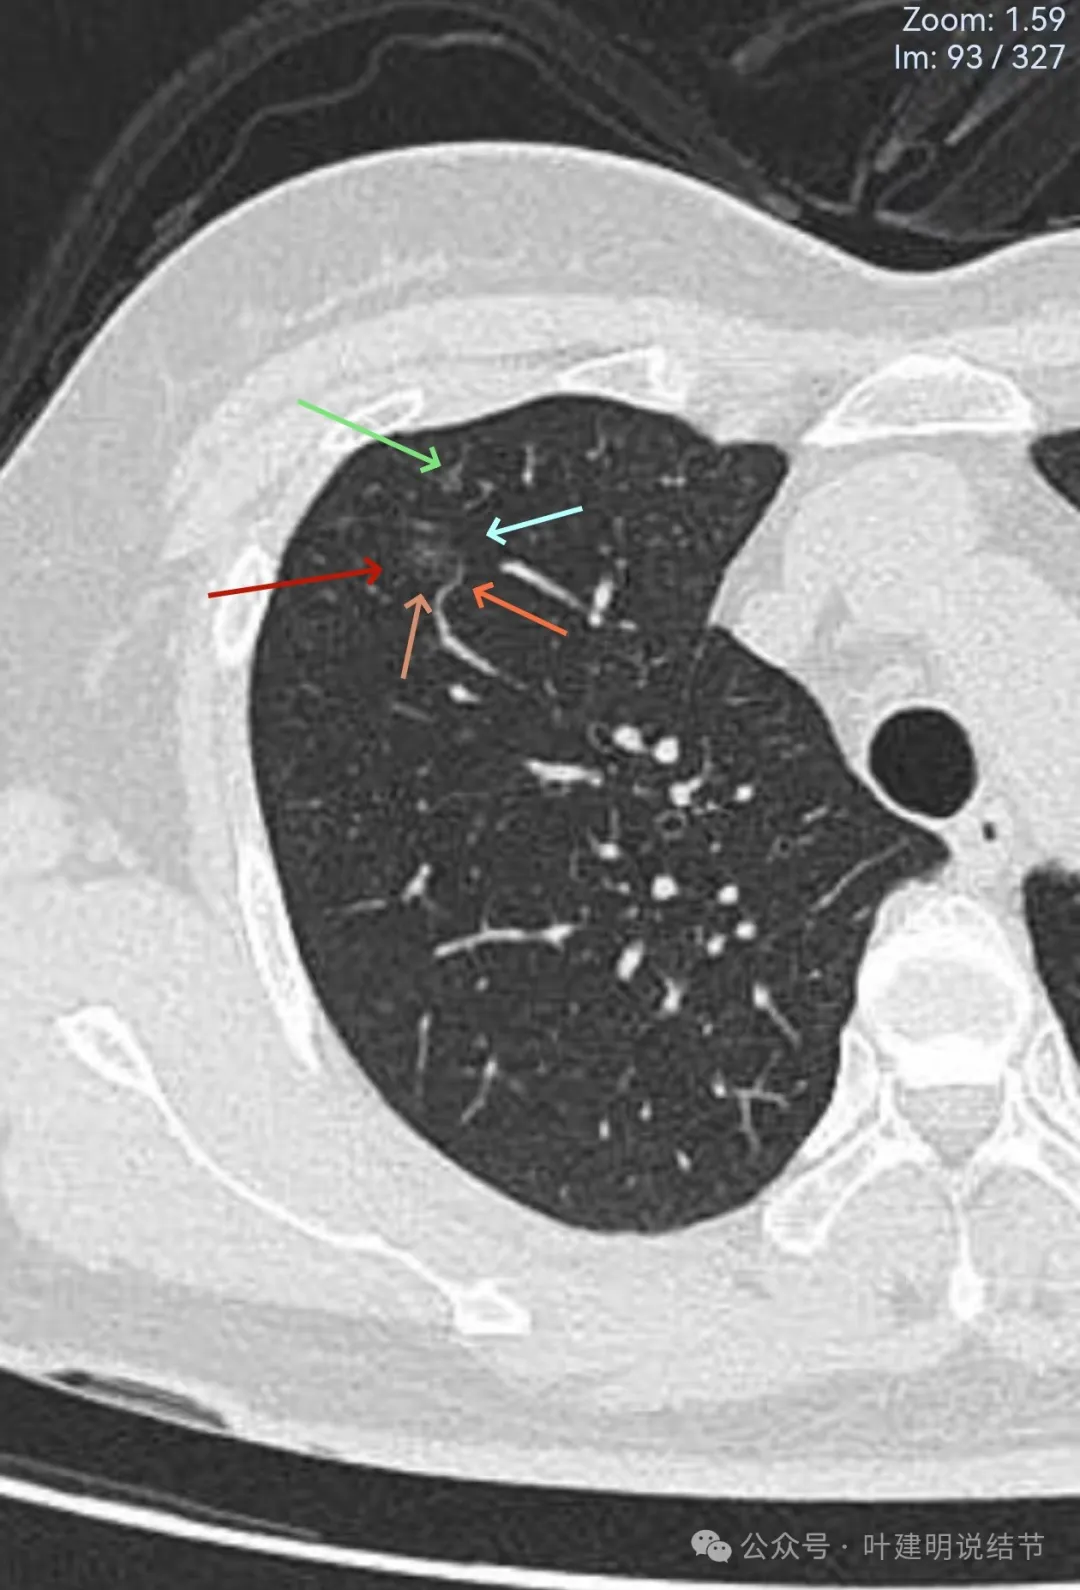

我的回复:

结友说所在的城市数一数二的医院,每次查了都拿给两家医院的影像科与胸外科主任看,但意见并不一致。结友强调我所不断提及的从风险出发为病人考虑的认识角度,是她深度喜欢的。我也认为自己的想法是正确的。